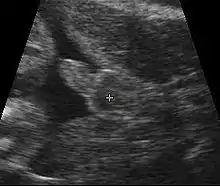

Obstetric ultrasonography, either transvaginally or transabdominally, checks for various markers of fetal sex. It can be performed at or after week 12 of pregnancy. At this point, 3⁄4 of fetal sexes can be correctly determined, according to a 2001 study.[53] Accuracy for males is approximately 50% and for females almost 100%. When performed after week 13 of pregnancy, ultrasonography gives an accurate result in almost 100% of cases.[53]